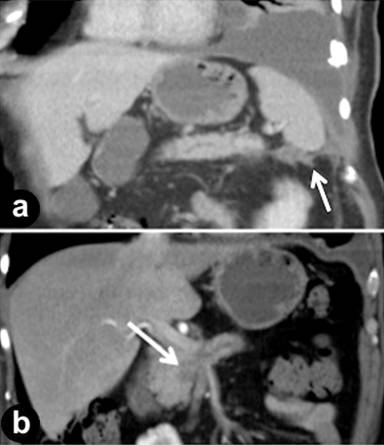

A 65-year-old gentleman presented with a history of worsening dyspnoea. A chest radiograph demonstrated a large left sided pleural effusion. A pleural drain was inserted and haemorrhagic pleural fluid was drained, which on cytological analysis contained benign inflammatory cells. Computed tomography (CT) of the thorax did not identify an underlying pulmonary lesion. However, the limited imaging of the left subphrenic region was suggestive of an inflammatory process in the region of the tail of the pancreas. The amylase level in a pleural fluid sample was found to be 23,225 IU/L suggestive of a pancreaticopleural fistula. A dedicated pancreatic protocol CT was thus performed (Figure 1). This demonstrated a small volume of rim enhancing fluid in the left upper quadrant tracking from the tail of the pancreas to the left hemidiaphragm, consistent with a pancreaticopleural fistula. Furthermore the main pancreatic duct was dilated with an abrupt cut off proximally at a 2.3 cm mass in the head of the pancreas, which was deemed surgically resectable by imaging criteria. A fine needle aspirate of the pancreatic mass was obtained under endoscopic ultrasound (EUS) guidance and yielded malignant cytology. Following a period of pre-operative optimization which included octreotide therapy and parenteral nutritional support, the patient underwent a pancreaticoduodenectomy. A histological diagnosis of pancreatic ductal adenocarcinoma was confirmed and a margin-negative resection was achieved. The post-operative period was unremarkable with full resolution of the pleural effusion. The patient is well and free of disease at the time of writing, six months postoperatively.

Figure 1. a. Reformatted coronal CT image shows a small volume of rim enhancing fluid in the left upper quadrant tracking from the tail of the pancreas to the left hemidiaphragm (arrow). A large left pleural effusion is also seen. b. Coronal CT image shows dilatation of the main pancreatic duct in the body of the gland with an abrupt cut-off in the region of the pancreatic head at the site of a 2.3 cm mass (arrow). |